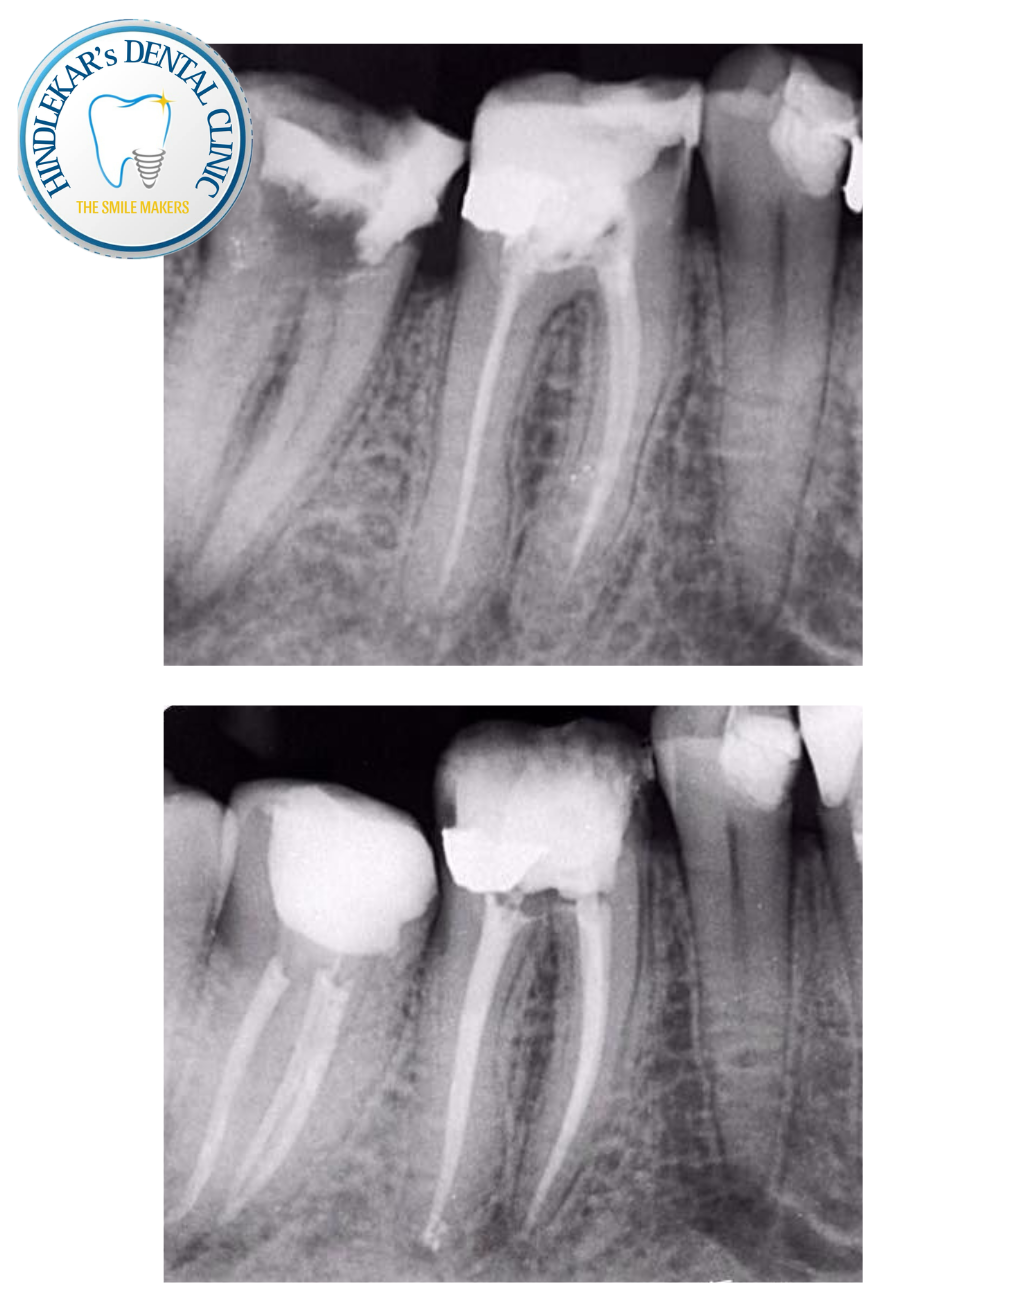

“Root Canal Failed? Don’t Worry!”

Still having pain after a root canal? Infection coming back? You may need a Re-Root Canal Treatment ✔ Save your natural tooth ✔ Advanced techniques & painless care ✔ Done by experienced specialist 📞 Book your consultation today at Dr Ajit Hindlekar’s Dental Clinic, Balewadi